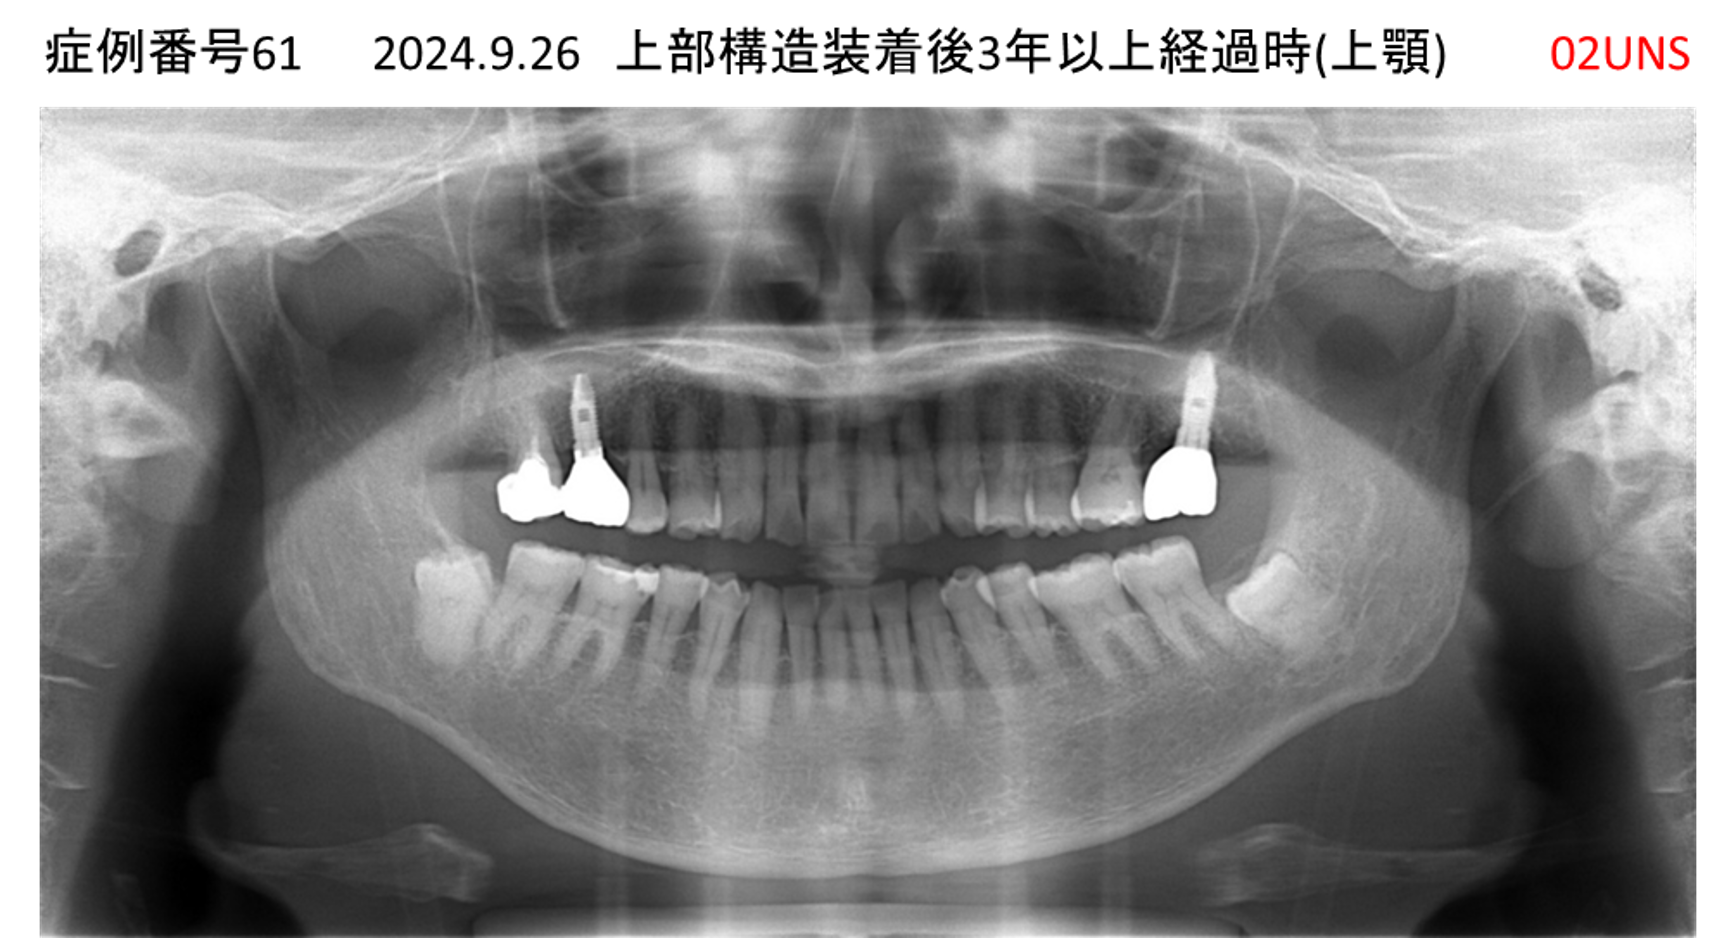

上の前歯が揺れている患者様のインプラント症例

| 治療名称 |

インプラント |

| 治療費用 |

130万円+税 |

| 治療期間 |

4か月 |

| 患者さんの症状(主訴) |

上の前歯が揺れているので何とかしてほしい。 |

| 治療内容 |

抜歯即時インプラント |

| 治療結果 |

見た目も歯の揺れもなく、とても快適。 |

| 治療の注意点(リスク/副作用) |

インプラントが壊れたら再治療が必要 |